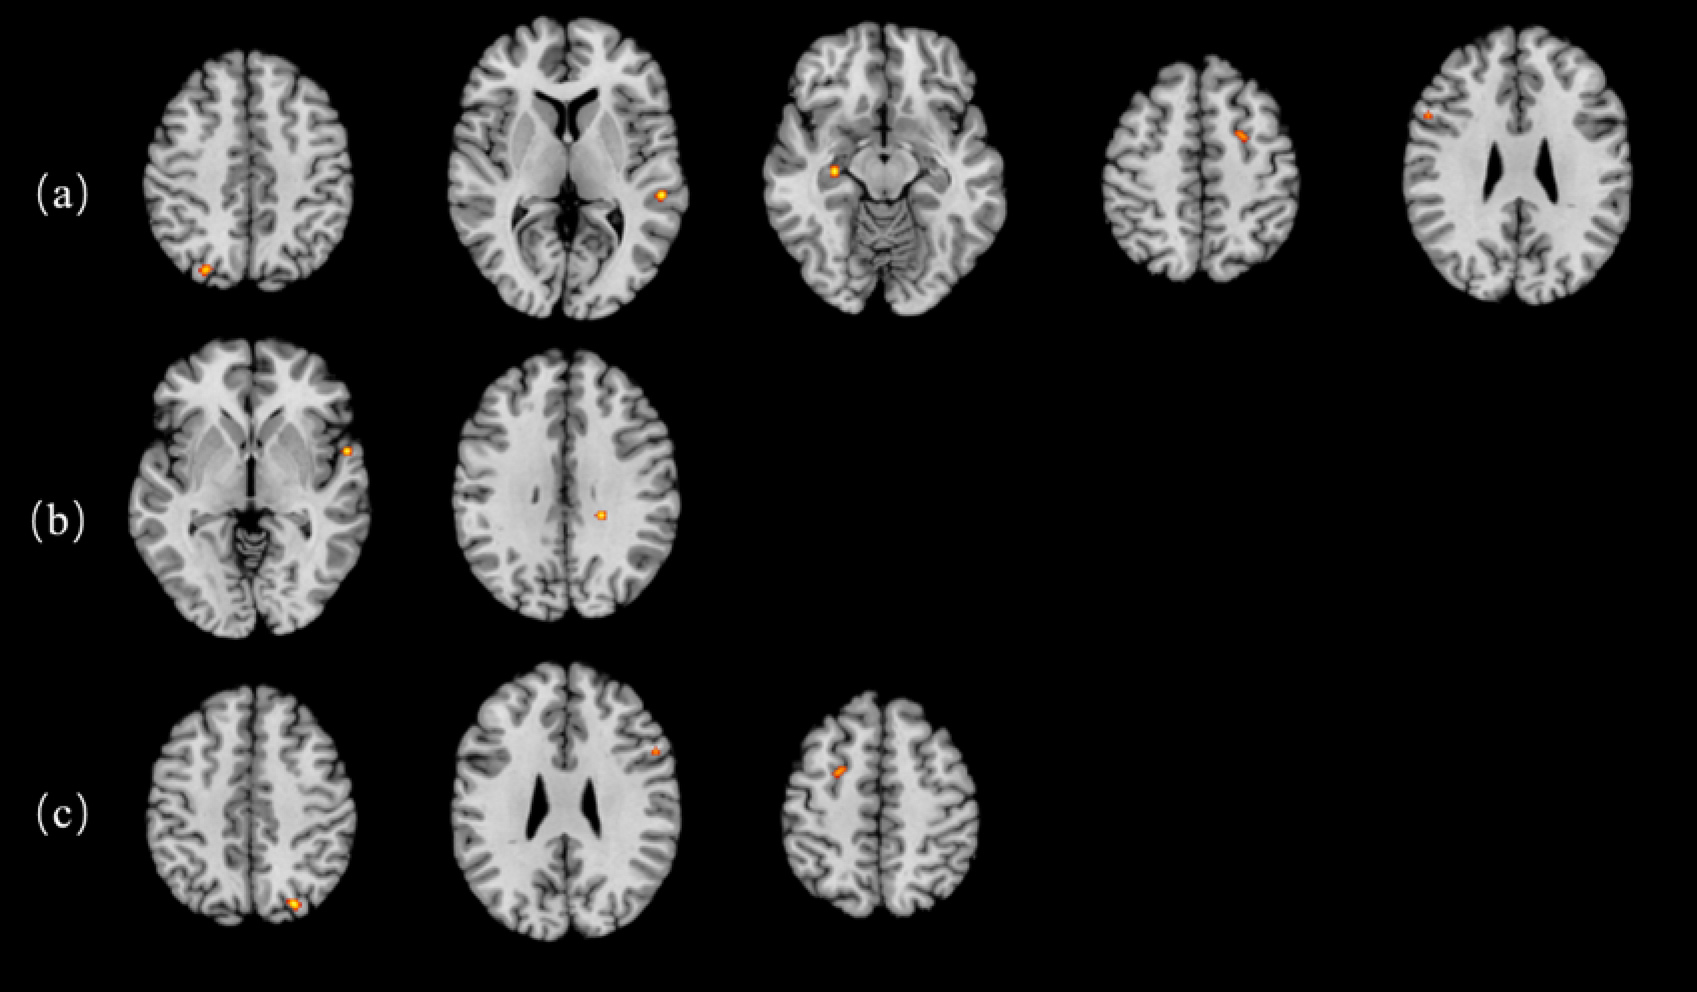

Fig. 2

Activation clusters for inhibition ALE analysis in standard MNI space. (a) Inhibition. (b) Incongruent. (c) Incongruent-congruent.